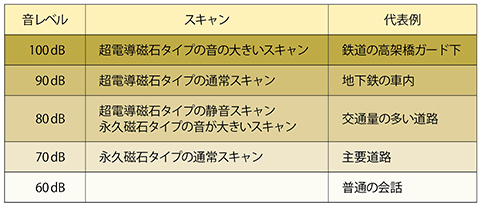

1.撮像音(表3)

MRIの撮像時の「音」は,静磁場強度に比例して大きくなります。撮像音はシーケンスや撮像条件などにより変化しますが,静磁場強度の低い永久磁石タイプは,どの撮像でもおおよそ80dB以下となっています。静磁場強度の高い超電導磁石タイプでは,撮像音を小さくするため,各社ハードウエアやソフトウエアによって音を抑える開発も進んでいます。

表3 MRIスキャンの音レベル